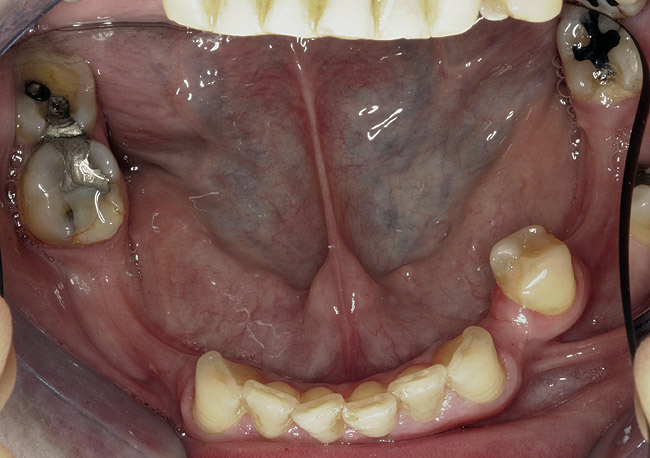

Figure 5  Intraoral occlusal view of mandibular dentition presenting excessive signs of wear.

Figure 5

Initial examination revealed a partial edentulous patient with extensive wear of the maxillary anterior teeth and moderate wear in the mandibular teeth (Figure 1, Figure 2, Figure 3 , Figure 4, Figure 5, Figure 6 and Figure 7). The patient's maxillary and mandibular RPDs also showed excessive wear and multiple signs of fractures (Figure 2 and Figure 3). The patient had been wearing a mandibular nightguard for 8 years.

A history of bruxing and consumption of acidic and carbonated drinks were reported. The clinical examination revealed severe tooth wear extending to the cervical level of the palatal surfaces of the maxillary teeth in some areas. Therefore, TSL was diagnosed as being caused by a combination of attrition and erosion.